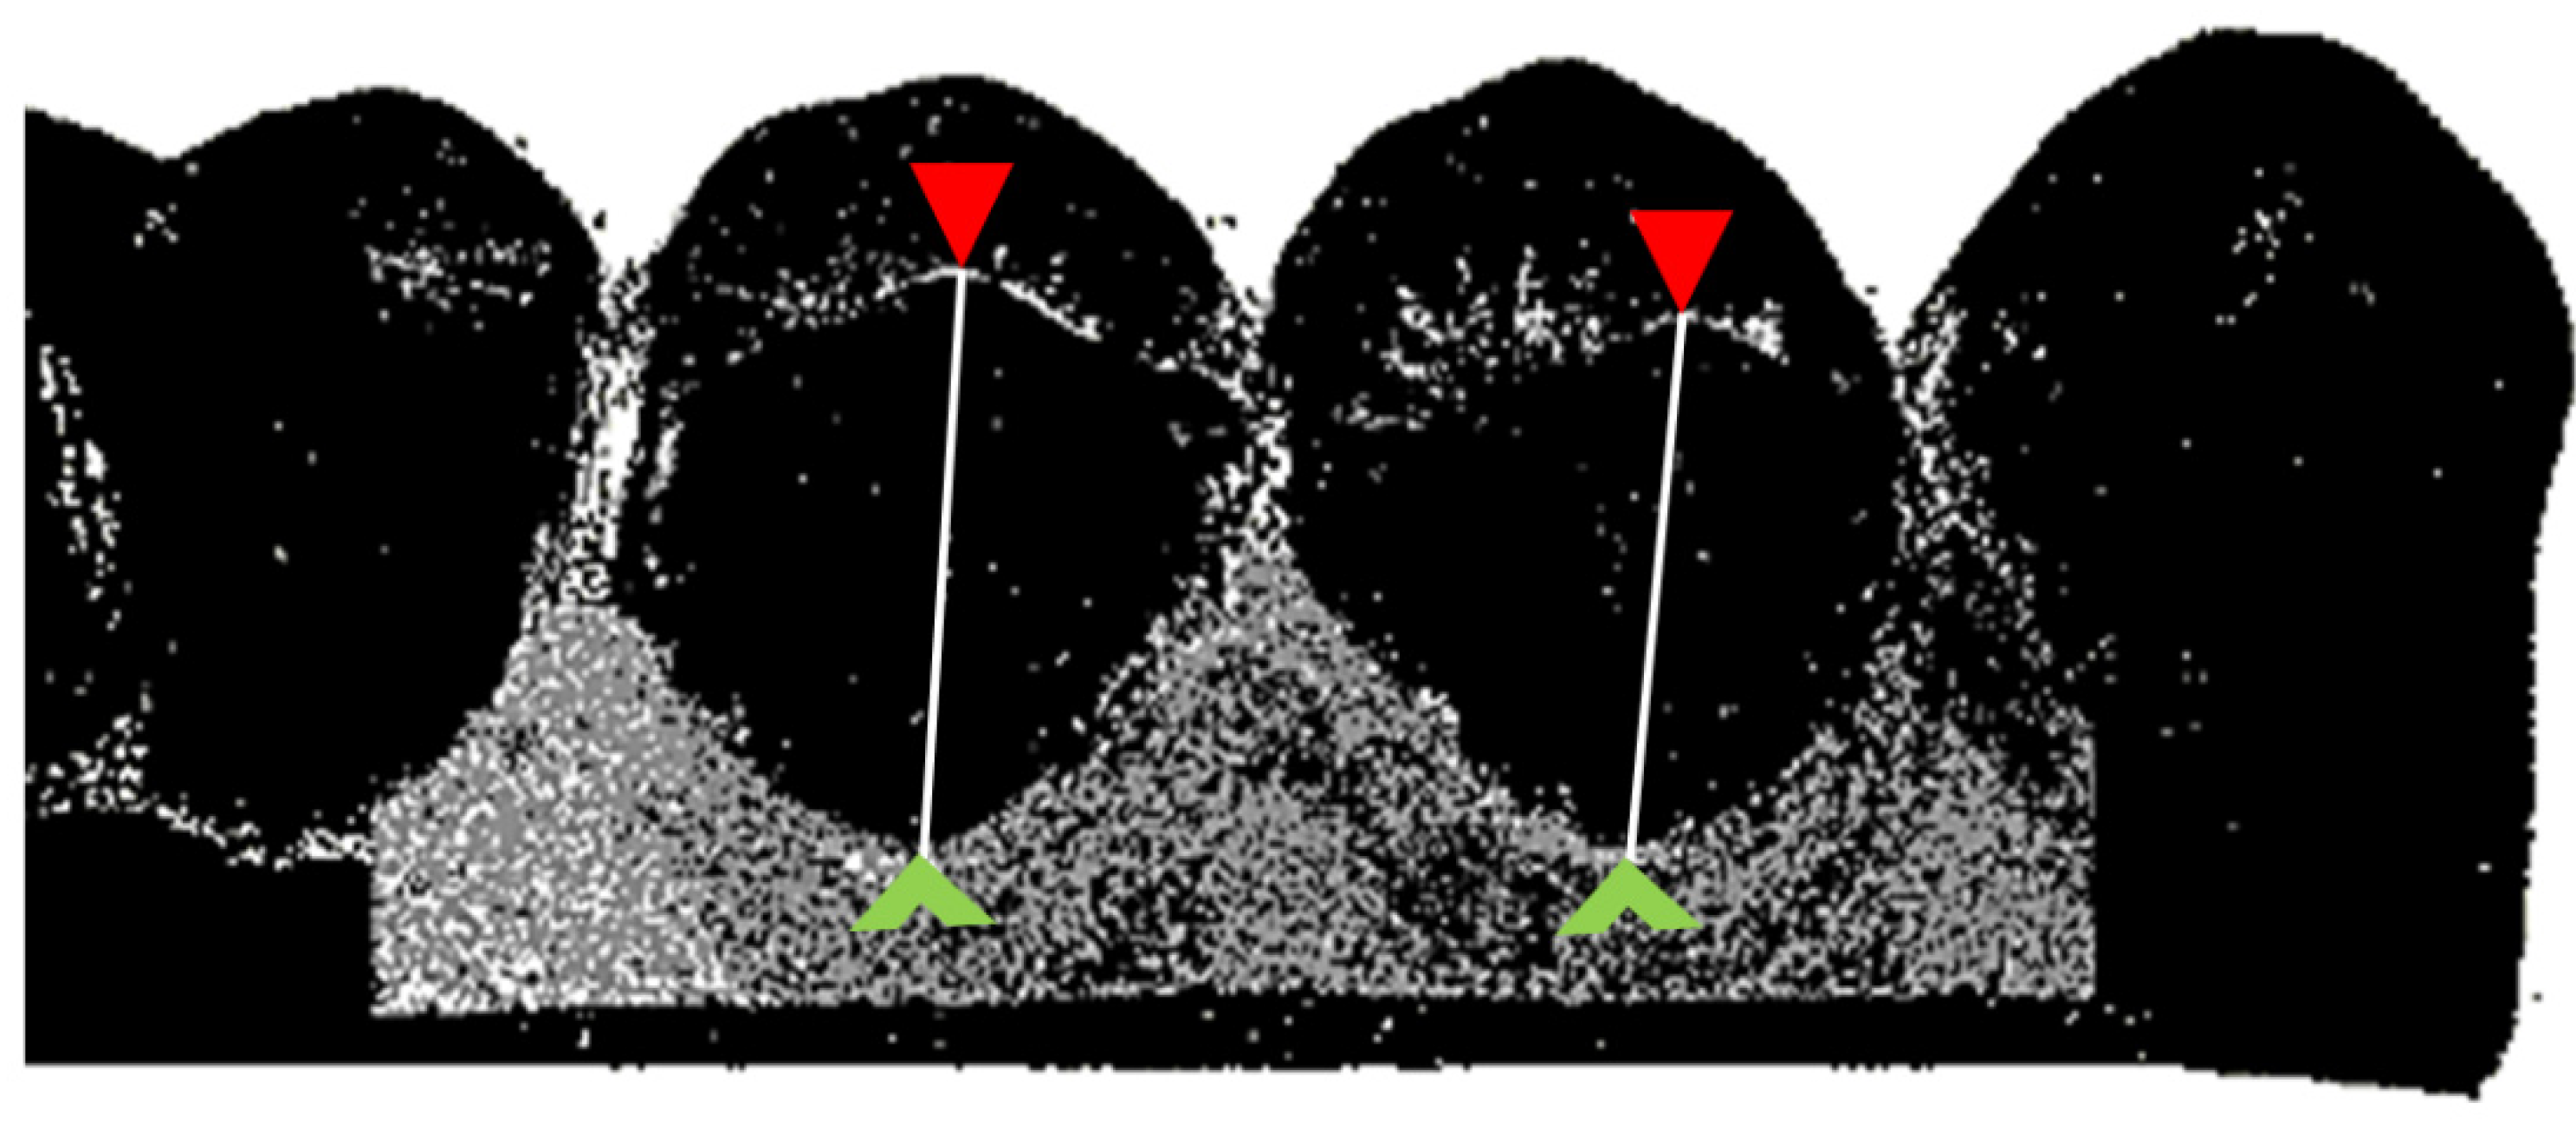

2.4.1. Sulcus Representation

2.4.2. Marginal Gingiva Height

- Luthardt, R.G.; Koch, R.; Rudolph, H.; Walter, M.H. Qualitative computer aided evaluation of dental impressions in vivo. Dent. Mater. 2006, 22, 69–76. [Google Scholar] [CrossRef] [PubMed]

- Rudolph, H.; Rohl, A.; Walter, M.H.; Luthardt, R.G.; Quaas, S. Performance of fast-setting impression materials in the reproduction of subgingival tooth surfaces without soft tissue retraction. Int. J. Prosthodont. 2014, 27, 366–375. [Google Scholar] [CrossRef] [PubMed][Green Version]